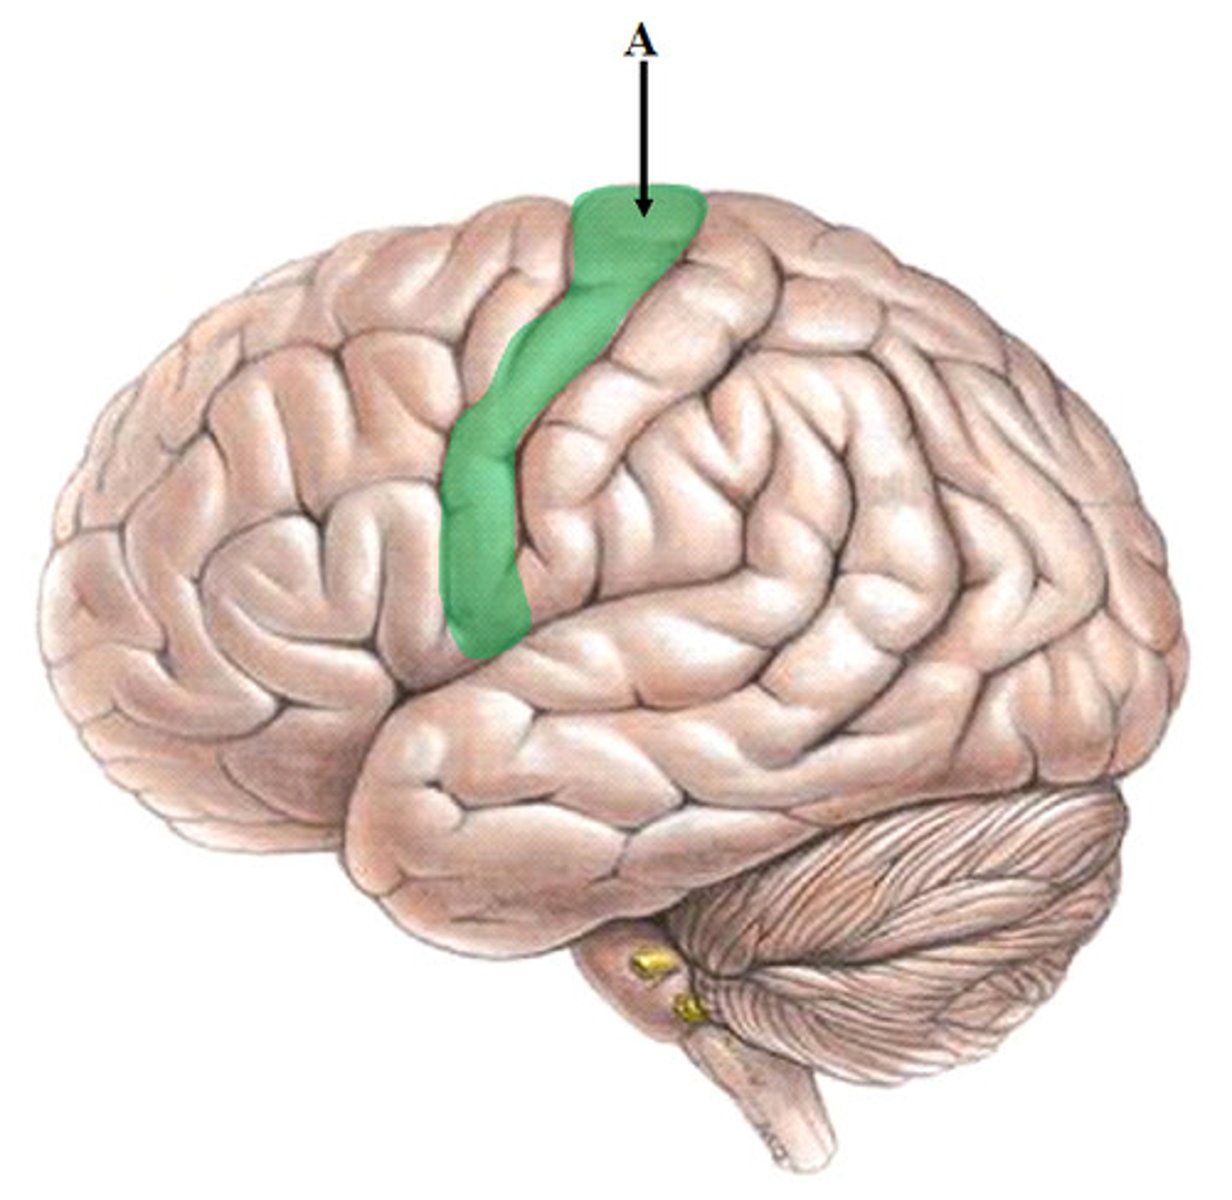

Superior Dorsal View of brain

Gyri

Sulci

Longitudinal Cerebral Fissure

Frontal Lobe

Parietal Lobe

Occipital Lobe

Central Sulcus

Lateral Sulcus

Somatomotor Area

Somatosensory Area

Cerebellum